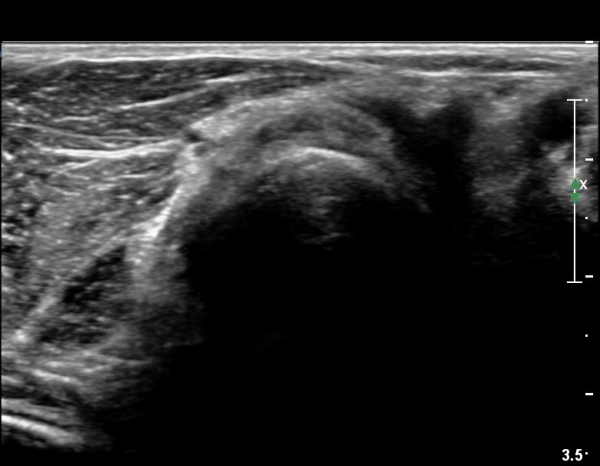

Á¶±Ý´õ ŽÃËÀÚ¸¦ ¸»´ÜÀ¸·Î À̵¿ÇÏ´Ï ³¶Á¾Àº ÀÛ¾ÆÁö°í ȸ¿Ü±Ù »çÀÌ¿¡ À§Ä¡ÇÏ´Â Èİñ°£ ½Å°æÀÇ

ºÎÁ¾ÀÌ °üÂûµÈ´Ù(»çÁø 6)